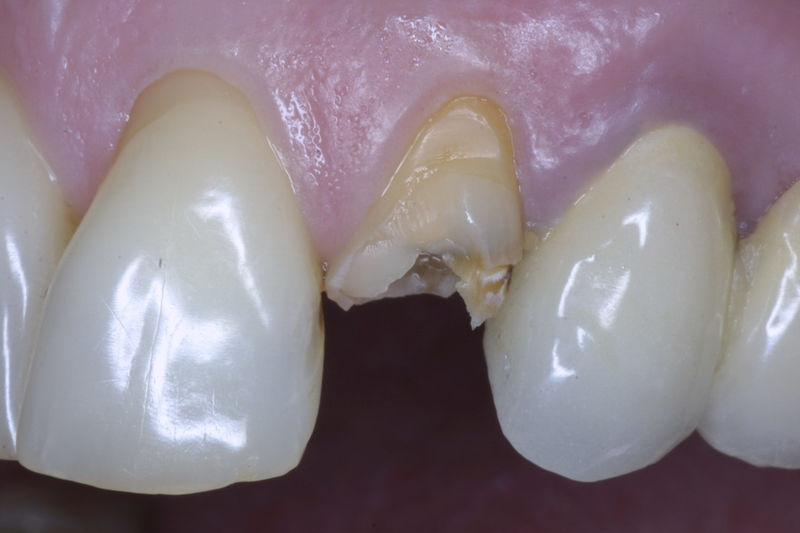

Restauraciones fabricadas en el laboratorio con materiales estéticos, los cuales cubren de manera total dientes anteriores y posteriores. Se utilizan primariamente para restaurar dientes con caries, fracturas y/o defectos amplios, así como soportes de puentes. Para poder enviar el caso al laboratorio se toman impresiones utilizando materiales de impresión o técnicas modernas digitales.